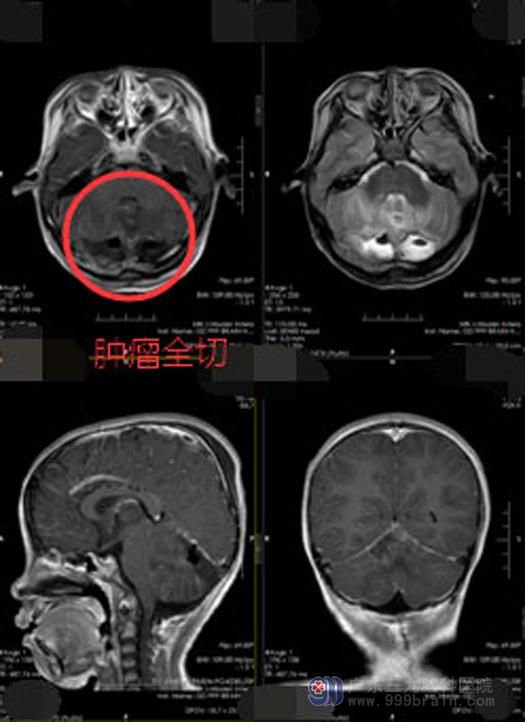

医院副院长、神经外五科主任鲁明带领团队制定了缜密的手术方案后,于11月25日在全麻下行“双侧小脑半球巨大肿瘤切除术+硬脑膜修补术+后颅窝去骨瓣减压术”,肿瘤血供丰富,双侧小脑半球水肿明显;沿小脑幕下切除部分小脑后,见肿瘤呈灰红色质地较软,边界清,肿瘤存在卒中,肿瘤主体位于幕下右侧小脑半球累及对侧,肿瘤沿小脑幕生长至深部达小脑幕与大脑镰结合部,沿边界边止血边全切除肿瘤。

术后当天,小妍意识清醒,生命体征平稳,四肢肌力正常。术后病理:(小脑)胚胎性肿瘤,WHOⅣ级。还需要转肿瘤科进行治疗。小妍爸爸说:虽然还在进一步治疗中,但是看着孩子精神越来越好,家里人也都充满了信心。